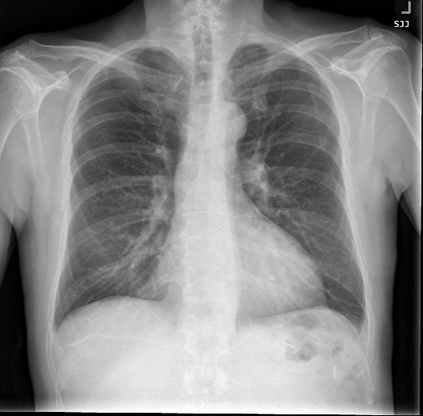

The remarkable success of deep learning has prompted interest in its application to medical imaging diagnosis. Even though state-of-the-art deep learning models have achieved human-level accuracy on the classification of different types of medical data, these models are hardly adopted in clinical workflows, mainly due to their lack of interpretability. The black-box-ness of deep learning models has raised the need for devising strategies to explain the decision process of these models, leading to the creation of the topic of eXplainable Artificial Intelligence (XAI). In this context, we provide a thorough survey of XAI applied to medical imaging diagnosis, including visual, textual, example-based and concept-based explanation methods. Moreover, this work reviews the existing medical imaging datasets and the existing metrics for evaluating the quality of the explanations. In addition, we include a performance comparison among a set of report generation-based methods. Finally, the major challenges in applying XAI to medical imaging and the future research directions on the topic are also discussed.